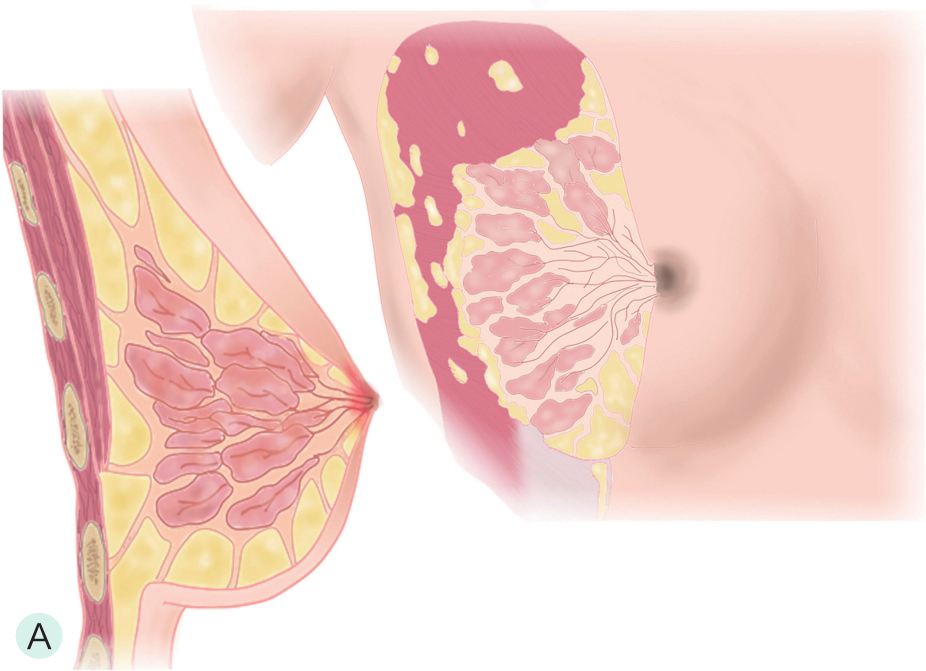

乳管系统为一由输乳管反复分支而呈现树状分支的结构单位,90%以上为2分支型,多分支型最多可达6分支,导管直径一般为2.0~4.5mm,随着导管分支逐渐变细。每个乳腺由15~20个腺小叶导管系统构成(图1-2-1A、图1-2-1B),每个系统组成一个乳腺叶,每个腺叶有其相应的导管系统,每个腺叶以乳头为中心呈轮辐样放射排列,各有一个导管向乳头引流,称输乳管(图1-2-1A),在乳头的基底部,距乳头开口约0.5cm处呈壶腹样膨大(图1-2-1C~图1-2-1E),口径为5~6mm,充满乳汁直径可达6~8mm,供暂时储存乳汁,该膨大区称乳窦。窦外末段输入管口径又缩小,并开口于乳头。从乳管开口到壶腹部的一段导管内衬以多层鳞状上皮细胞,以下的中小导管及腺泡内衬单层柱状细胞。若单个导管内的上皮细胞增殖呈乳头状突入管腔,称为导管内乳头状瘤。乳腺癌主要来源于腺管的柱状上皮细胞,发生于腺泡的癌仅占5%。

图1-2-1 乳腺结构与影像图

A.乳腺模式图;B.乳腺小叶声像图;C、D.乳腺导管声像图;E.乳腺扩张导管MRI图